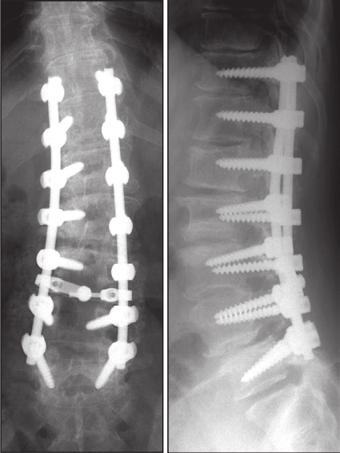

(5)半坚强固定

据文献报道,半坚强固定可使得近端建立从僵硬固定区到非融合区有一个平缓的过渡,避免在上固定椎区域有一个应力的集中,可以避免交界性后凸的发生。

图36 多棒固定向两棒固定的过渡

图37 半坚强固定